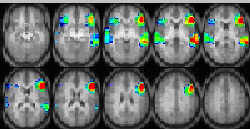

Figure 2.

Figure 2. R-Map. Z-score compared to childhood mean blood lead levels. In Broca’s area, a negative correlation to childhood blood lead level is shown in blue. In the homolog of Wernicke’s area, a (+) correlation to childhood blood lead level is shown in yellow and red.

A composite Z-map (N = 43 subjects) reveals the activation associated with the verb-generation task (Figure 1). The regions typically associated with language apparent in this cohort include the traditional Broca’s area, Wernicke’s area, and the dorsolateral prefrontal cortex with overall left hemispheric dominance. An R-map compares the Z-score for predefined language regions of interest (ROIs) with a lead exposure index based on the mean of analyzed blood samples collected quarterly from birth to 5 years and at 5.5, 6, and 6.5 years (Figure 2). After adjusting for FSIQ in 41 subjects, activation in the left frontal inferior gyrus, where the traditional Broca’s area is located, demonstrated a significant inverse correlation with the mean childhood lead level (R = -0.39, p = 0.01) (Figure 3). Activation in the right temporal region, the contralateral area to the traditional Wernicke’s area, showed a strong positive correlation with the mean childhood lead level (R = 0.35, p = 0.03) (Figure 4).

The results of the fMRI study of semantic language, specifically a verb-generation task, reveal that lead exposure during childhood alters brain activation. Reduced activation in Broca’s area, a recognized region of language function in the left hemisphere, correlated with FSIQ-adjusted, elevated childhood blood lead levels. Increased activation in the right temporal lobe, the homolog of Wernicke’s area in the left, correlated with FSIQ-adjusted, elevated childhood blood lead levels. These correlations suggest a damaging effect to the traditional language areas by childhood lead exposure. These findings are consistent with other neurobehavioral studies finding language deficits, such as word recognition, associated with elevated childhood lead exposure.

Childhood lead exposure strongly influences neural substrates of semantic language function demonstrated as a selective, deleterious effect on normal language areas with concomitant recruitment of contra-lateral regions, resulting in striking, exposure-dependent, atypical organization of language function.